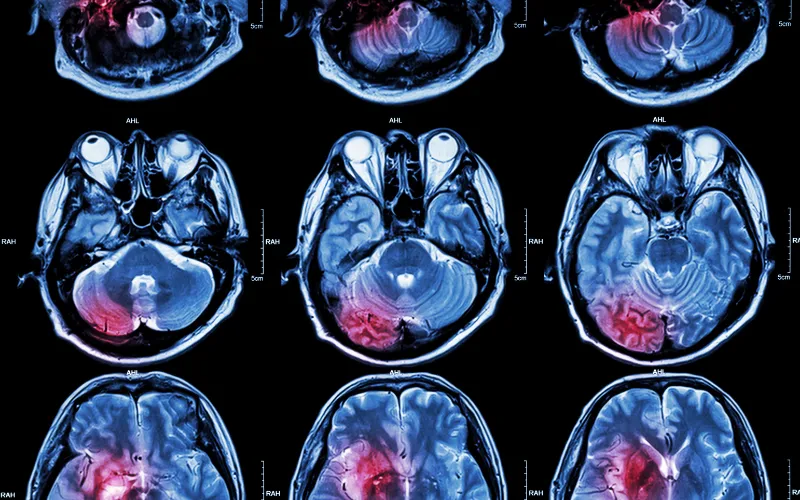

xray of a brain

Brain Tumor Center

The Brain Tumor Center at Dana-Farber/Boston Children’s is a world-renowned destination for children with malignant and non-malignant brain and spinal cord tumors.